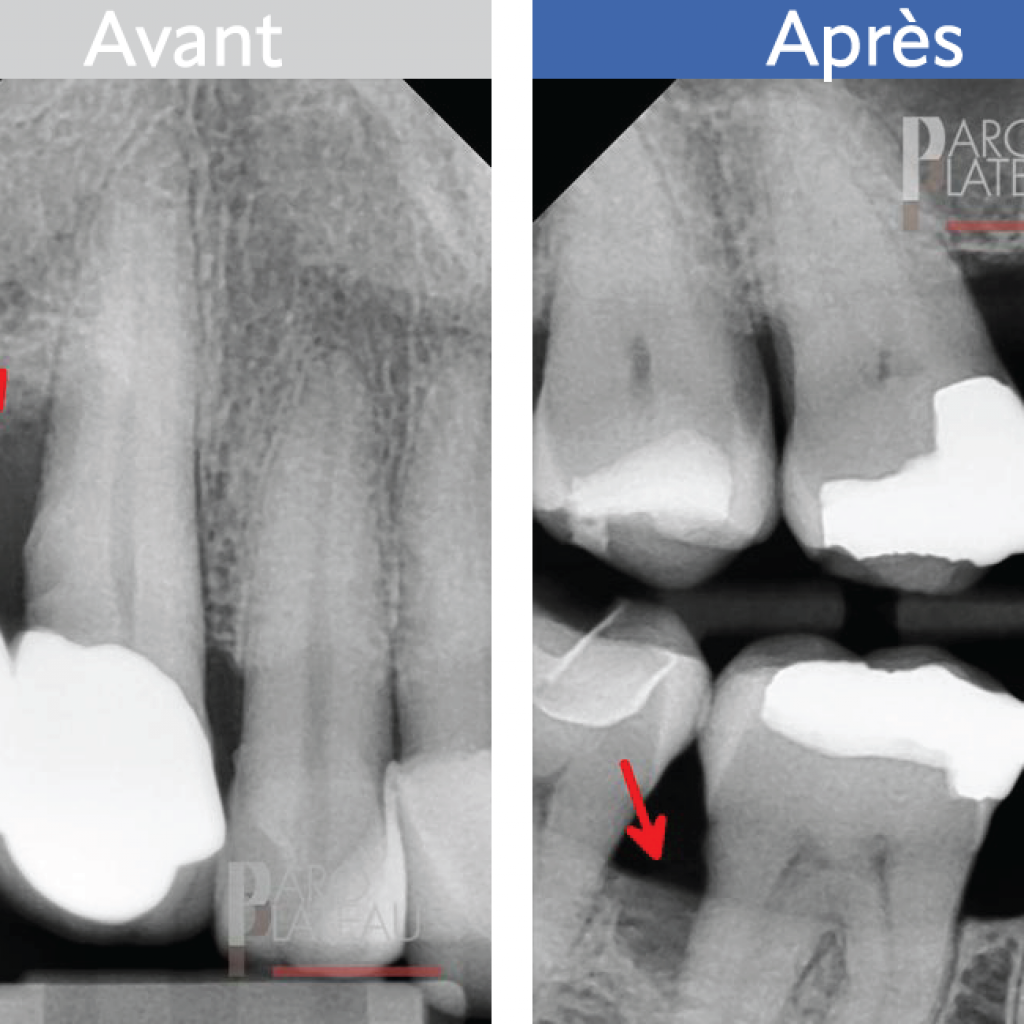

L’élongation coronaire

Cette procédure est nécessaire lorsqu’une carie profonde ou la fracture d’une paroi d’une dent se produisent. Il faudra alors dégager le pourtour de la dent afin de la rendre accessible à la restauration.

Avant

Après